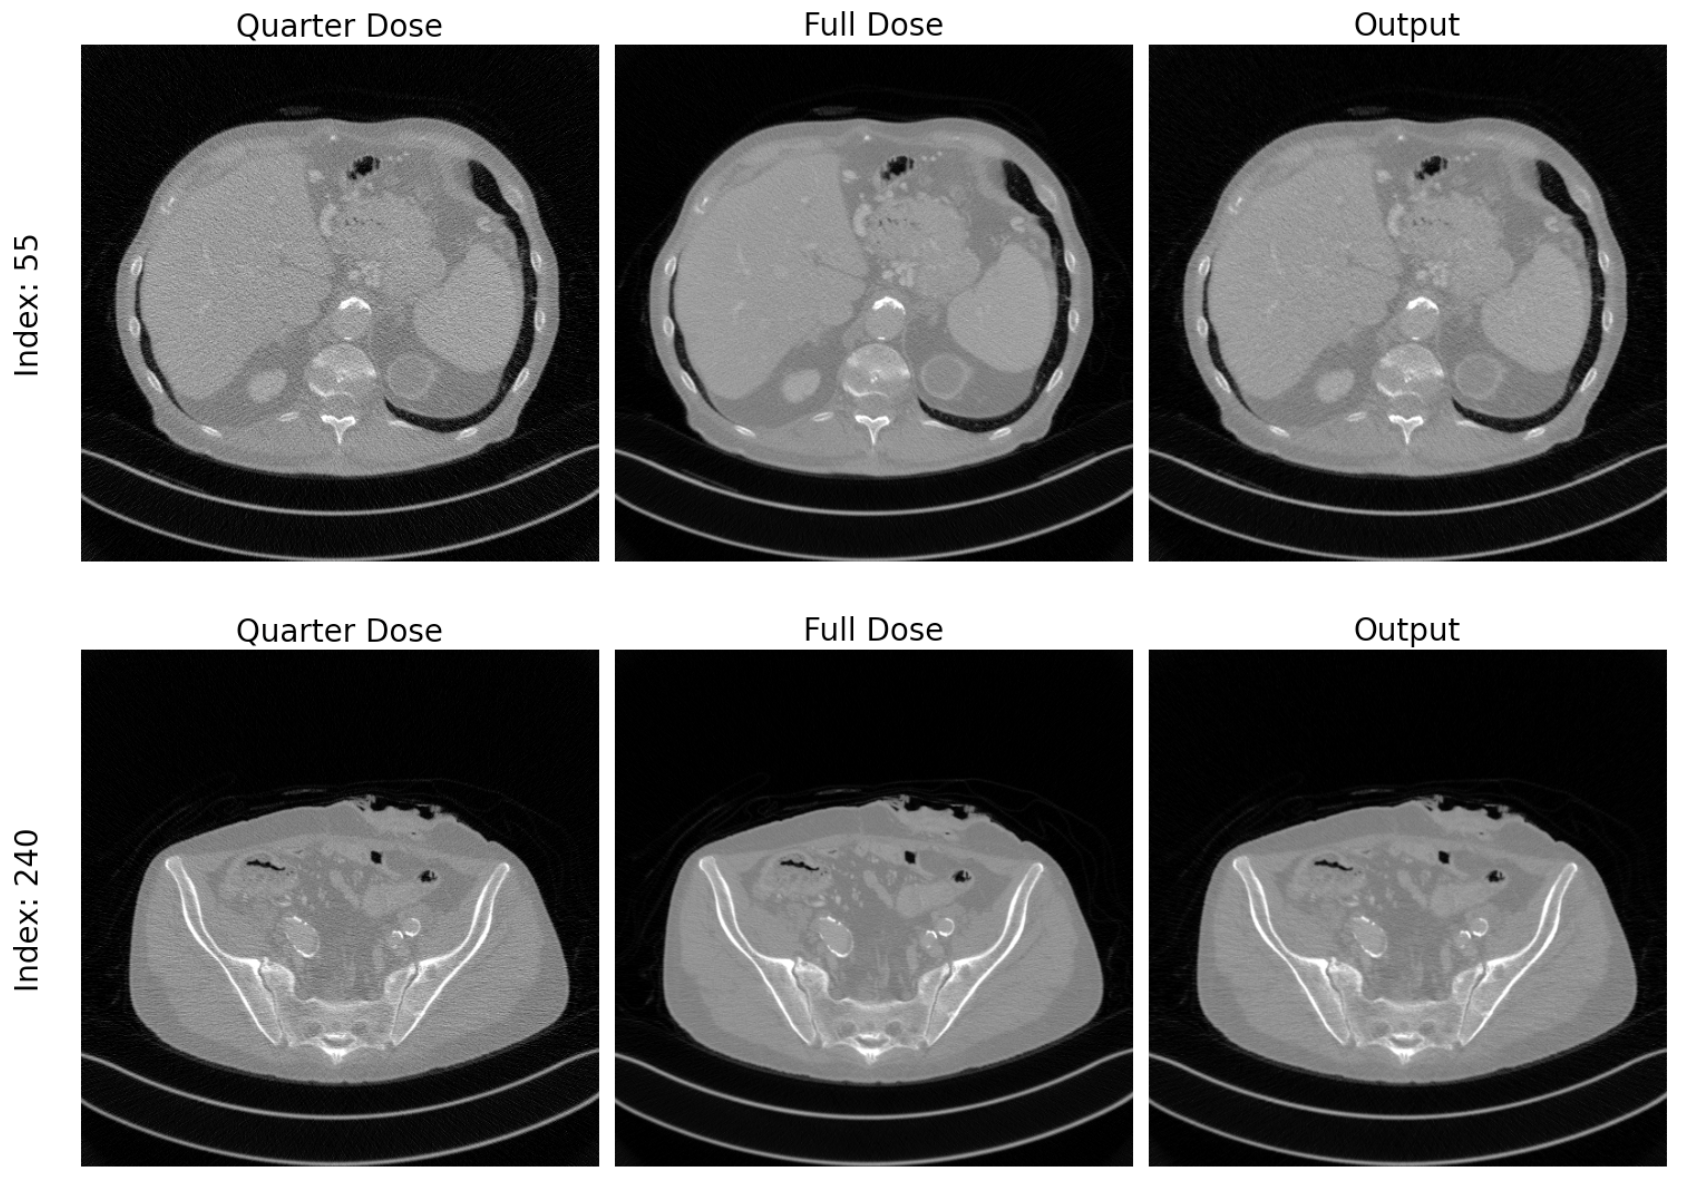

CT Denoising CycleGAN

Low-Dose CT Image Denoising via Unpaired Image-to-Image Translation

• CycleGAN to denoise quarter-dose CT images into full-dose quality without paired training data

• Compared CycleGAN losses vs. supervised losses for CT image quality enhancement

Keywords: CycleGAN, Medical Image Denoising, Unpaired Image Translation